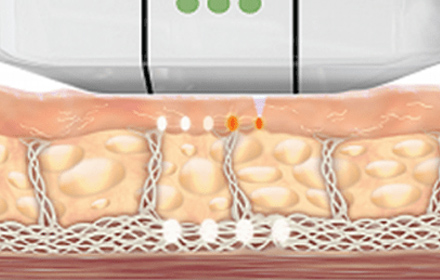

울쎄라피 프라임은 1.5mm, 3.0mm, 4.5mm

세 가지 팁으로 진피부터 근막층(SMAS)까지

타겟팅이 가능해 피부 상태에 따라 맞춤 시술이 가능합니다.

울쎄라피 프라임은 새로운 콜라겐 생성 및 재생을 위한

최적의 온도인 60~70도의 열을 표적조직에 정확하게 전달합니다.

초음파 에너지를 SMAS층까지 집속시켜

전달하여 콜라겐 재생을 촉진시킵니다.

피부 표면에 손상없이 SMAS층을 응고, 수축시켜

콜라겐 재생 및 처짐이 개선됩니다.